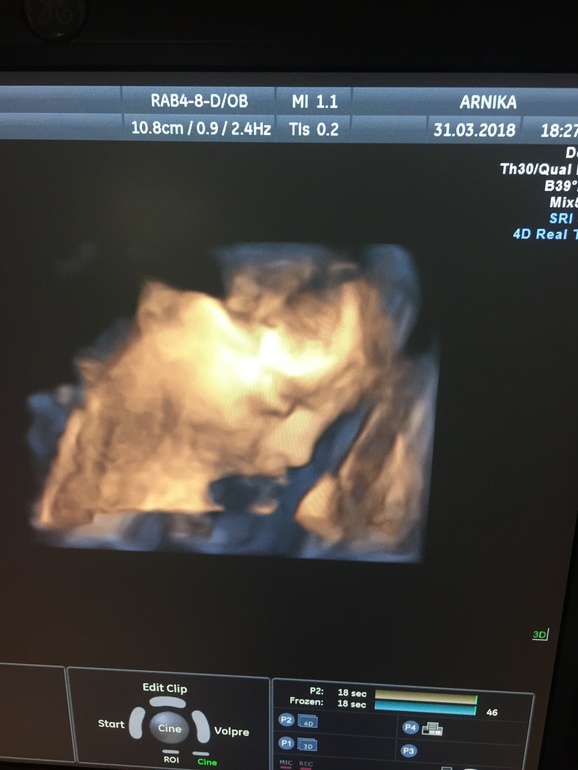

26 недель, УЗИ 3Д

УЗИ, КТГ, доплерЗдравствуйте девушки, интересно ваше мнение, расскажу немного пред истории. Пошли мы неделю назад смотреть на нашу малышку, любопытство берет свое на кого же она похожа) И оказалась, что визуализация затруднена из-за низкой плаценты 2 см всего, хотя нужно 6. И поставили гипертонус, хотя на 2 скрининге все было в порядке( Я грешу на себя как раз занимались ремонтом вещи туда сюда тоскали. Еще после оргазма замечала, что матка как в "кучу" собирается. Узиолог спросила принимаю ли я что то, утрик или магний, но я ни то, не другое не пила и не ставила. Решила самостоятельно назначить себе утрик 200 на ночь. Врач моя в отпуске, только 10 апреля к ней пойду. И теперь думаю правильно я сделала или нет. Прилагаю фото: 3д узи, матки в "кучке" и как мы подросли)